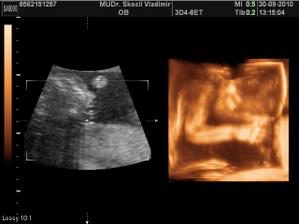

26.8. 2010 - 3D ultrazvuk, nádherný zážitek hlavně pro tatínka - všechno v pořádku, mimísek krásně roste.

Jen stále nevíme, zda čekáme holčičku nebo chlapečka - né že by byl mimísek stydlivej, ale spíš tvrdohlavej po tatínkovi, sveřepě

ležel na bříšku a ne a ne se otočit 🙂

16.9.2010 - 3D ultrazvuk, stále pohlaví nevíme a pan doktor je už docela dost zvědavý na naše mimi zepředu, stále se nám líbí na bříšku 🙂

30.9.2010 - 3D ultrazvuk - velký ultrazvuk ve 20 tt

Krásně rosteme, vážíme přesně 339 g a dokonce krásně spolupracujeme k nafocení všech částí těla, co pan doktor potřebuje.

Zatím to nevíme na 100 %, ale vypadá to, že čekáme chlapečka !